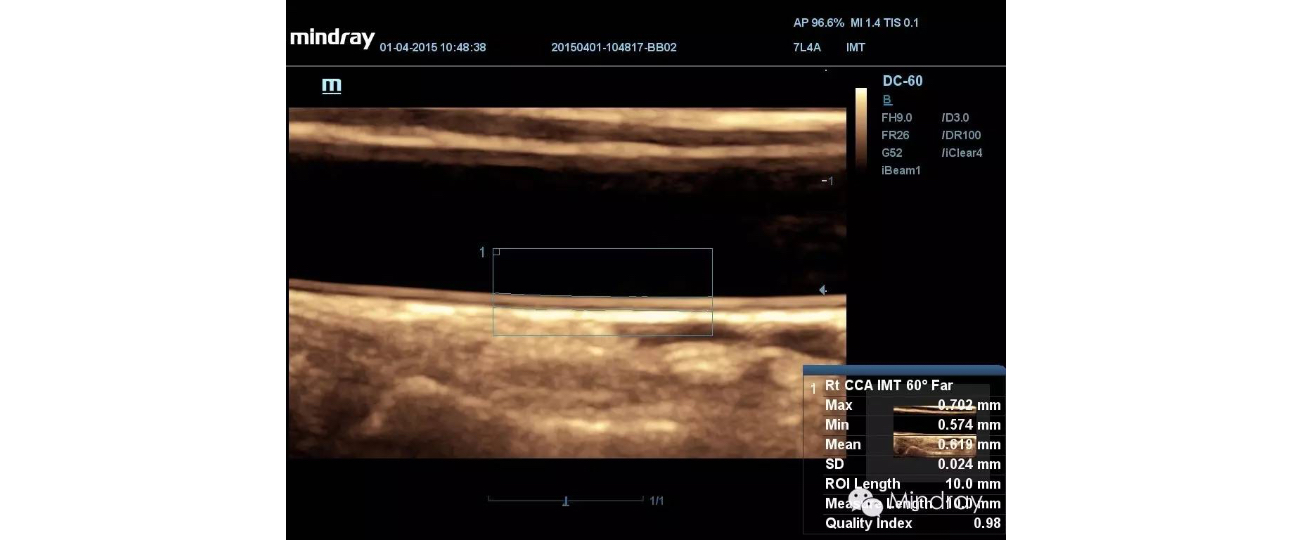

Based on DC-60's shared service capabilities, reliable image quality for patients of various ages and sizes in diverse clinical areas is available all with one intelligent ultrasound machine. Covering general imaging, cardiology and OB/GYN, the DC-60 has professional tools such as Auto IMT, iNeedle, TDI and QA, 4D imaging and Smart OB to help complete daily exams easily and precisely.

Auto IMT